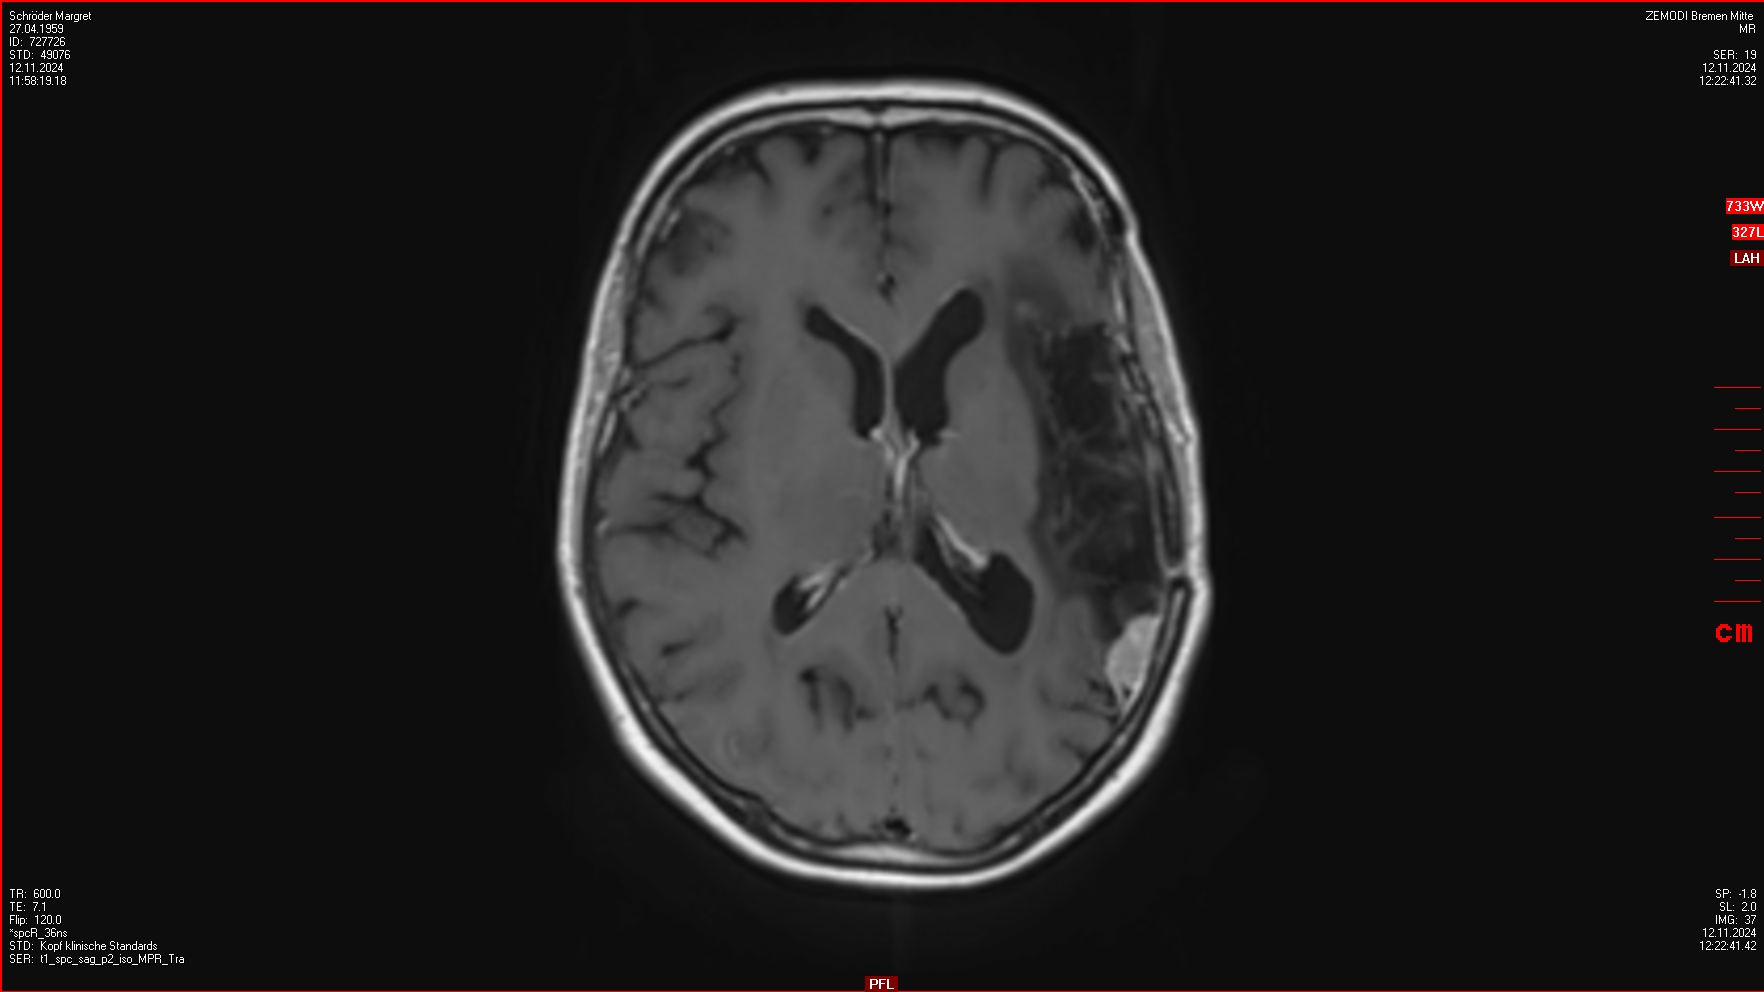

04.12.2024

OP im Krankenhaus Bremen-Mitte: 4 Menigeome (WHO III) entfernt, einige weitere verbleiben.

Auswertungen des MRTs wurden von Zemodi, eines Neurochirugen vom Klinikum Bremen-Mitte sowie von Prof. Lippitz gemacht. Das Ergebnis war identisch. Keine Aussage zum Wachstum der am 23.01.2025 bestrahlten Tumore.

Auswertungen des MRTs wurden von Zemodi, eines Neurochirugen vom Klinikum Bremen-Mitte sowie von Prof. Lippitz gemacht.